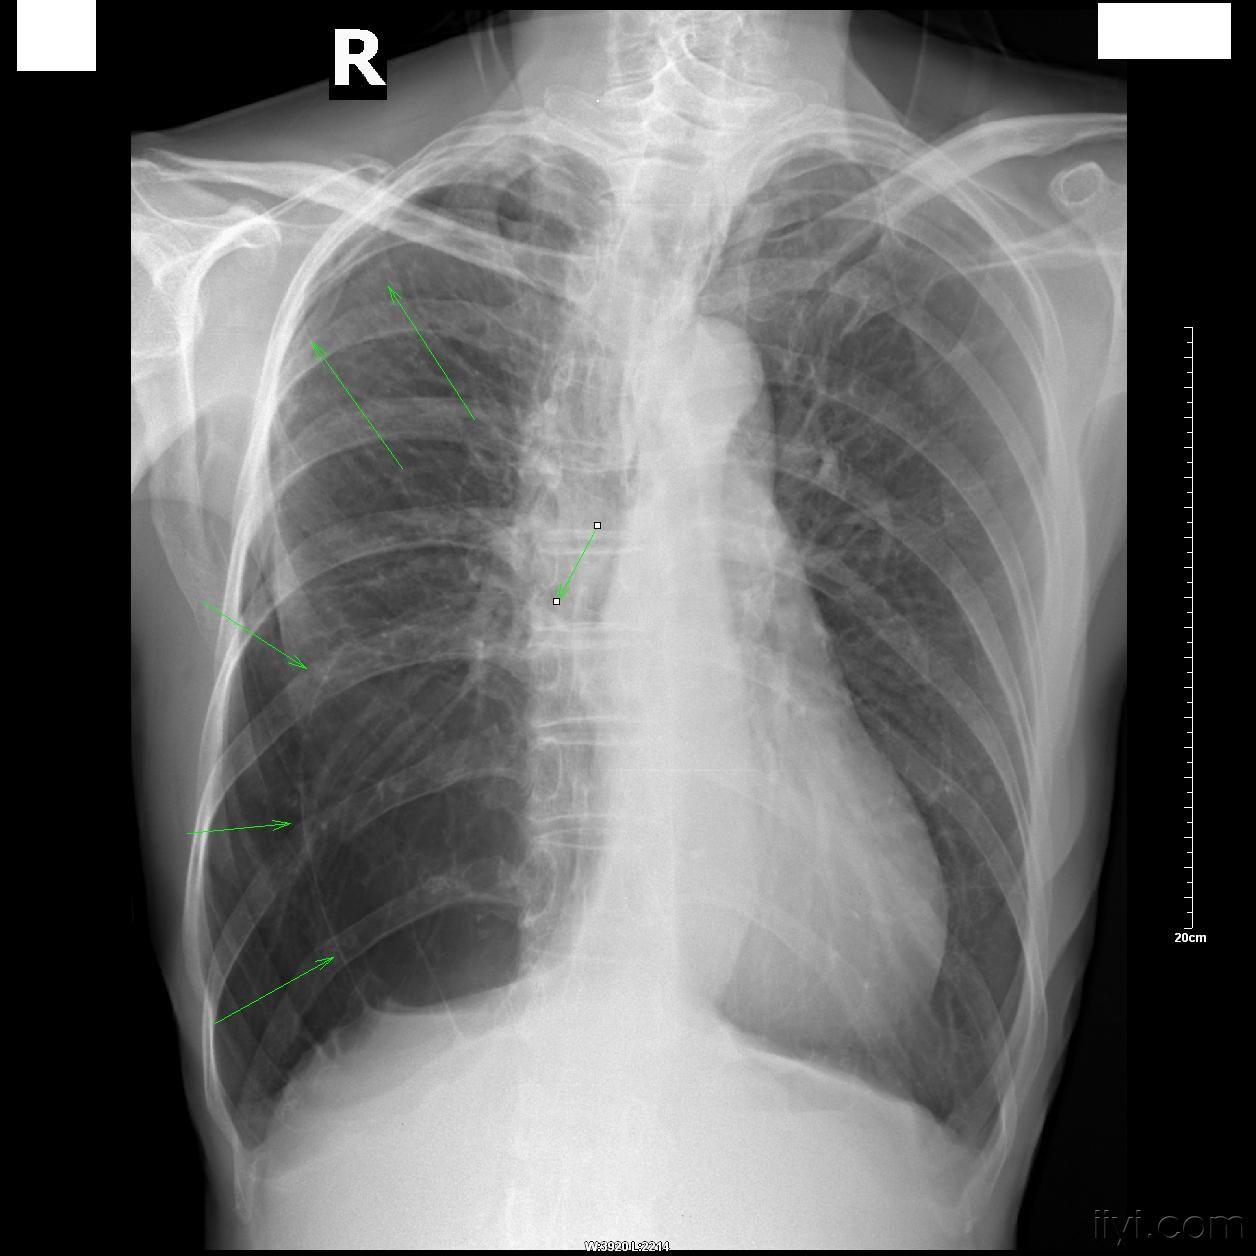

双侧多发肺大泡一例